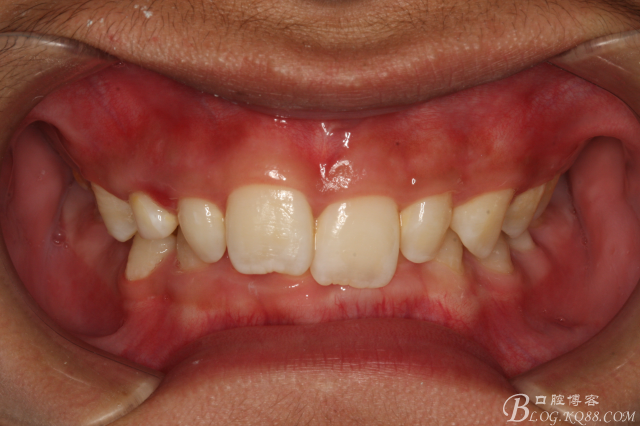

患者、李xx、男、14歲。主訴:牙齒排列不齊,要求正畸治療。??茩z查:右側(cè)乳尖牙滯留,13腭側(cè)粘膜輕度腫脹。CBCT檢查:13位于腭側(cè)。處理:建議拔除右側(cè)乳尖牙,并外科開窗牽引導(dǎo)萌13?;颊咄庵委煼桨?。簽知情同意書。

圖2.右側(cè)位咬合影像:乳尖牙滯留